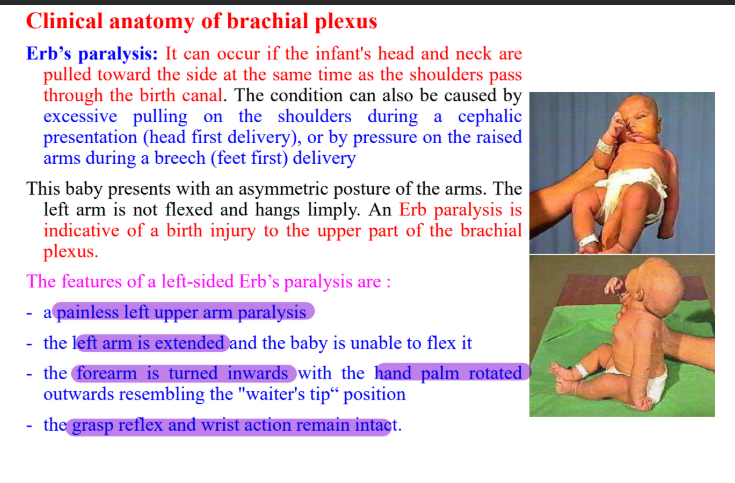

Clinical anatomy of brachial plexus